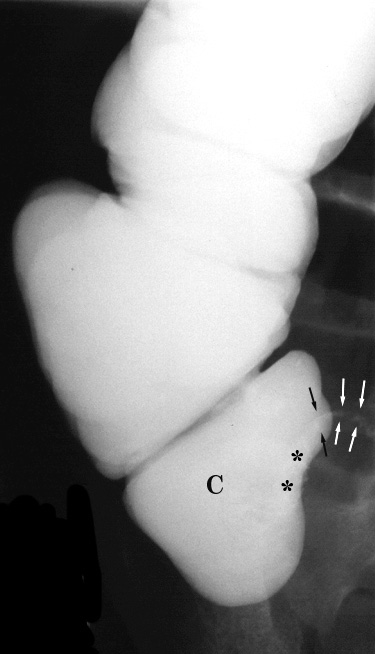

| Perforated appendicitis mimicking small bowel

obstruction. 4 year old girl presented with a four day history of anorexia, nausea, and vomiting. Physical examination was significant for pain on rectal examination. Plain films, a barium enema, and CT examination were obtained, shown below. |

|  | Figure 3. Spot compression view of the cecum (C) during single contrast barium enema demonstrates mass effect upon its medial border (*). Note the irregular margins of the partially opacified appendix (arrows). |